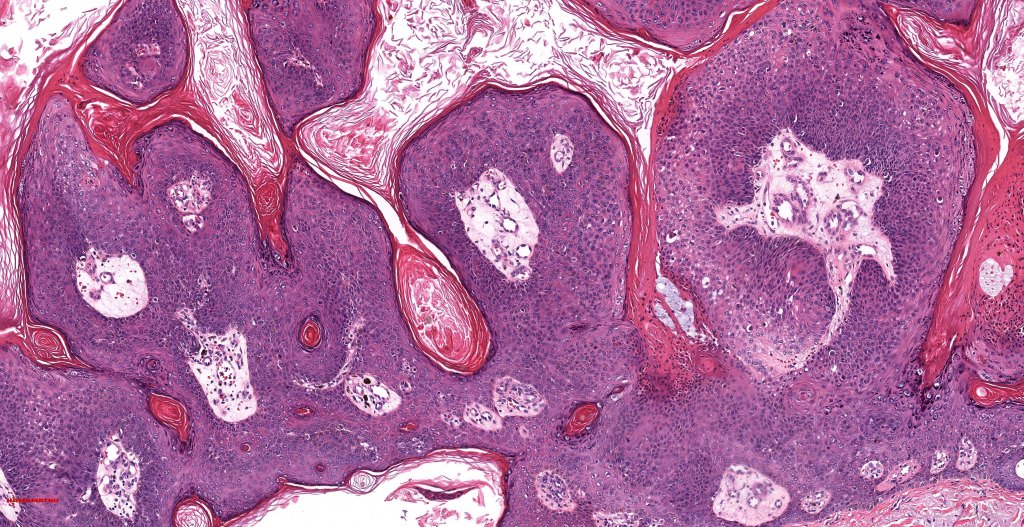

•Admixture of squamous carcinoma & pleomorphic spindled cell, osteoid, chondroid, MFH-like +/- osteoclast-like giant cells & rarely, smooth muscle, skeletal muscle, myofibroblastic or angiosarcomatous elements

•Epithelial component AE1/AE3, CK5/6 & p63 +ve;

•Mesenchymal element variable CD10, CD68, CD99 & lineage specific markers +ve; scattered cells may show weak keratin expression